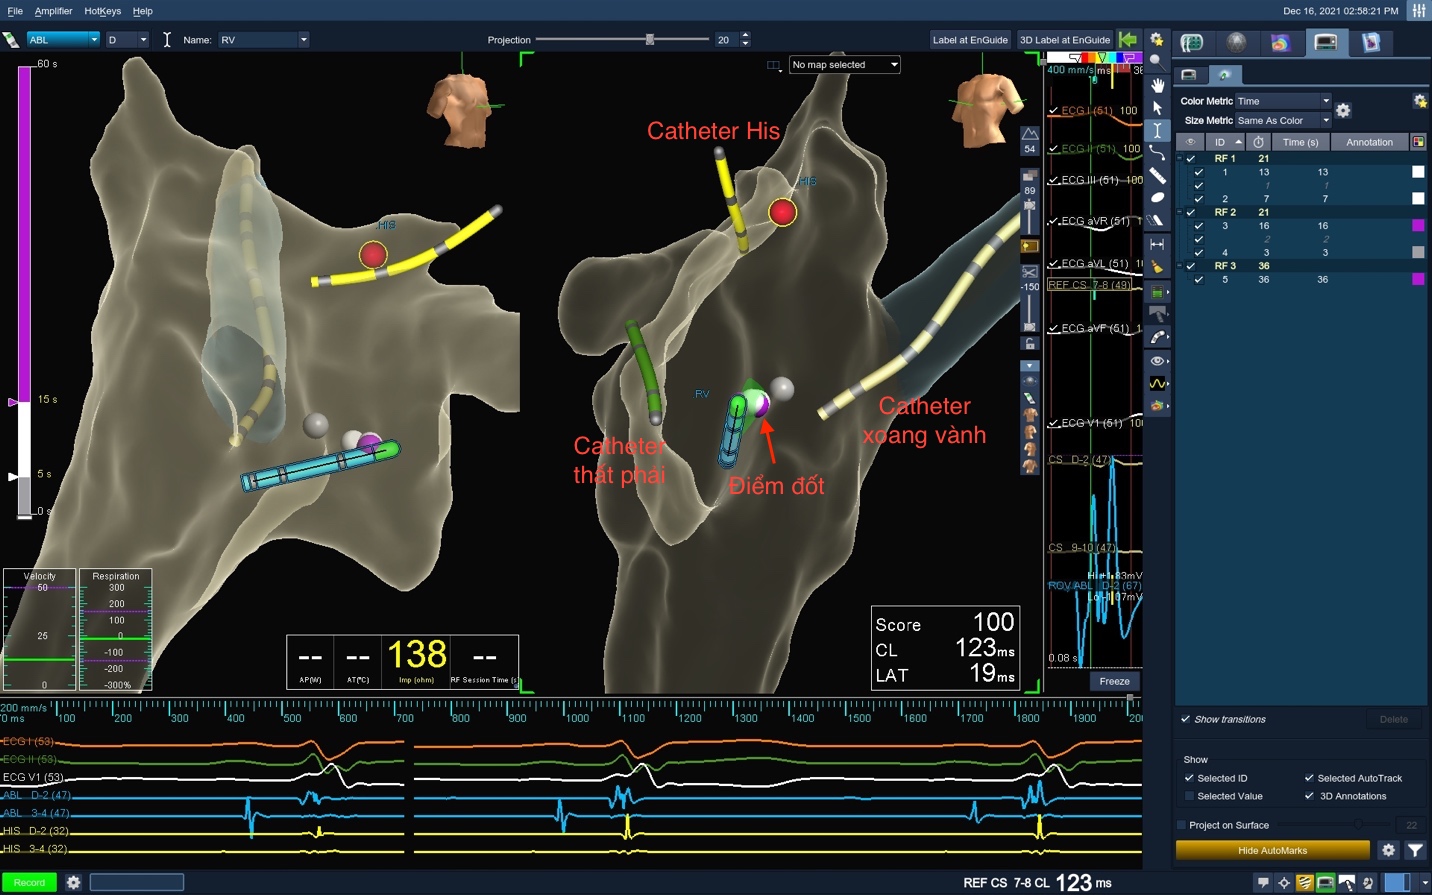

Thủ thuật được thực hiện bằng hệ thống điện sinh lý kết hợp với hệ thống lập bản đồ tim Ensite 3D NavX.

Dựng hình tĩnh mạch chủ dưới từ tĩnh mạch đùi đến nhĩ phải bằng catheter xoang vành.

Dựng hình 3D các cấu trúc trong tim gồm nhĩ phải, vòng van ba lá và xoang vành dưới hướng dẫn của hệ thống 3D.

Đặt các catheter chẩn đoán dựa trên mô hình 3D và chỉ sử dụng khoảng 1.2 giây tia X cho các bước khảo sát cần thiết.

Tiến hành cắt đốt đường dẫn truyền chậm và đánh dấu vị trí cắt đốt thành công trên hệ thống 3D.